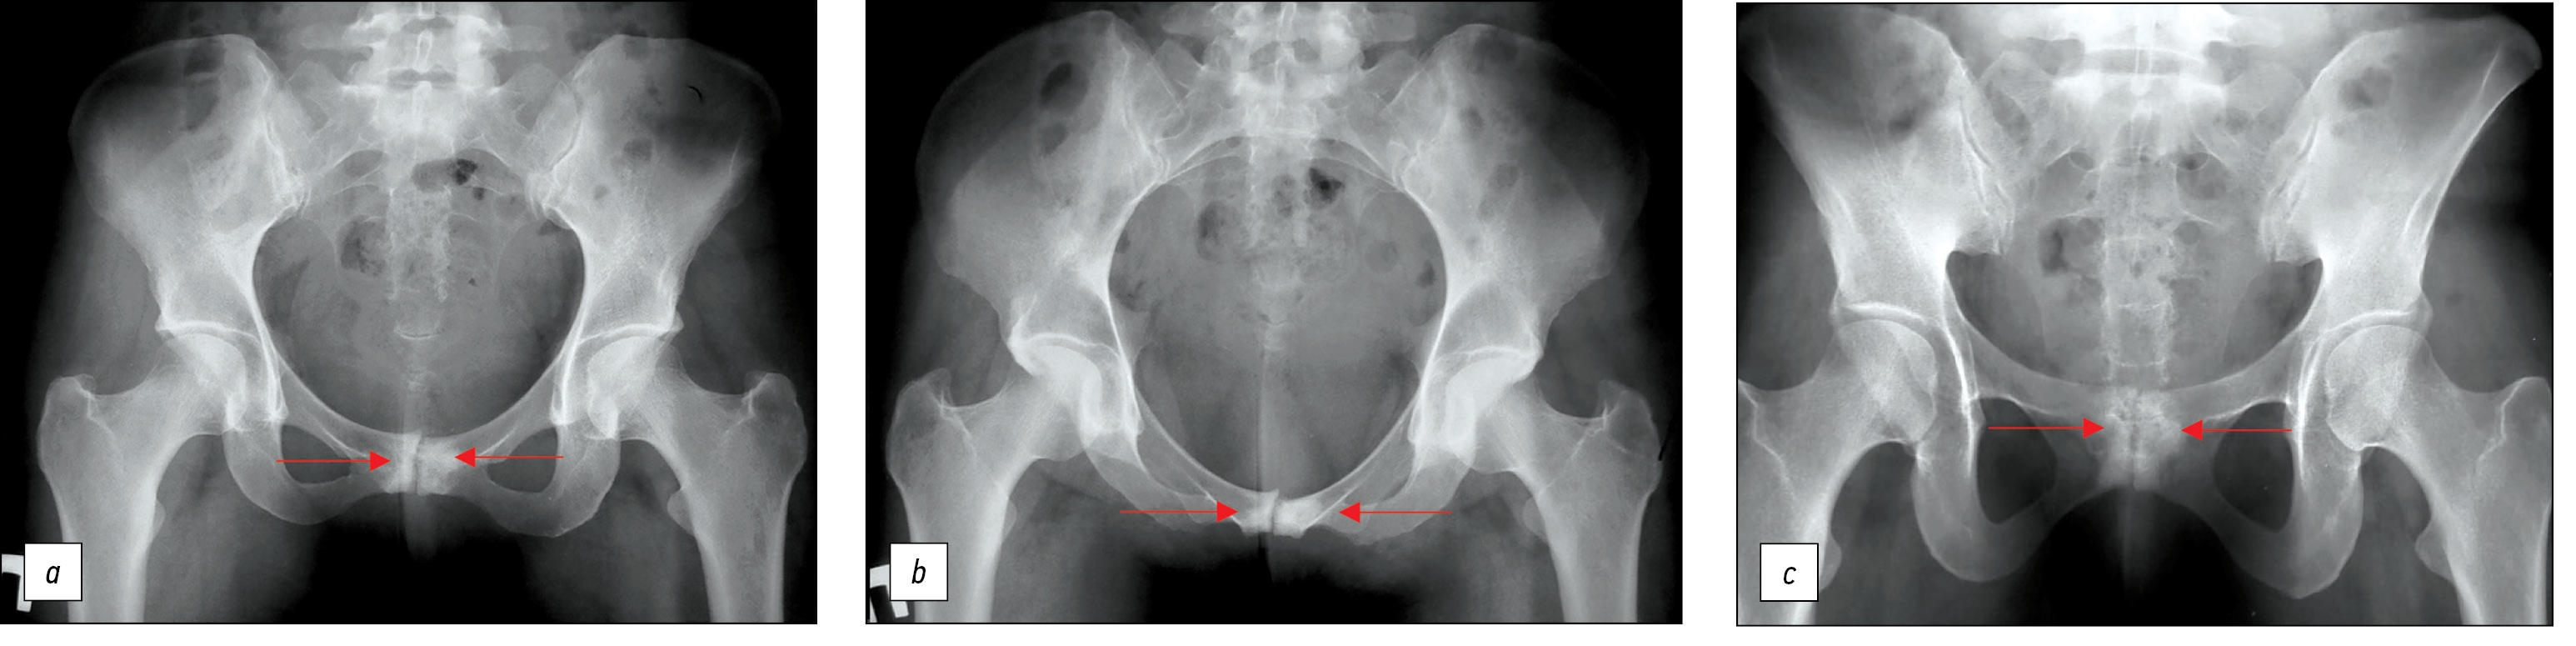

На рентгенограммах от 12.04.2021: признаки узурации зоны лобкового симфиза (рис. 5).

Рис. 5. Пациентка Г., 39 лет. На рентгенограммах видны признаки узурации лонного сочленения.

а — переднезадняя проекция, b — каудальная проекция, c — краниальная проекция.

Fig. 5. A 39-year-old patient on radiographs signs of pubic symphysis occlusion. a — anterior-posterior projection, b — caudal projection, c — cranial projection.

Рис. 8. Контрольные рентгенограммы пациентки Г. после операции. a — переднезадняя проекция, b — каудальная проекция, c — краниальная проекция (резекция лобкового симфиза, металлодез переднего полукольца таза пластиной).

Fig. 8. Control radiographs after surgery. a — anterior-posterior projection, b — caudal projection, c — cranial projection (Resection of the pubic symphysis, metal fusion of the anterior half-ring of the pelvis with a plate).